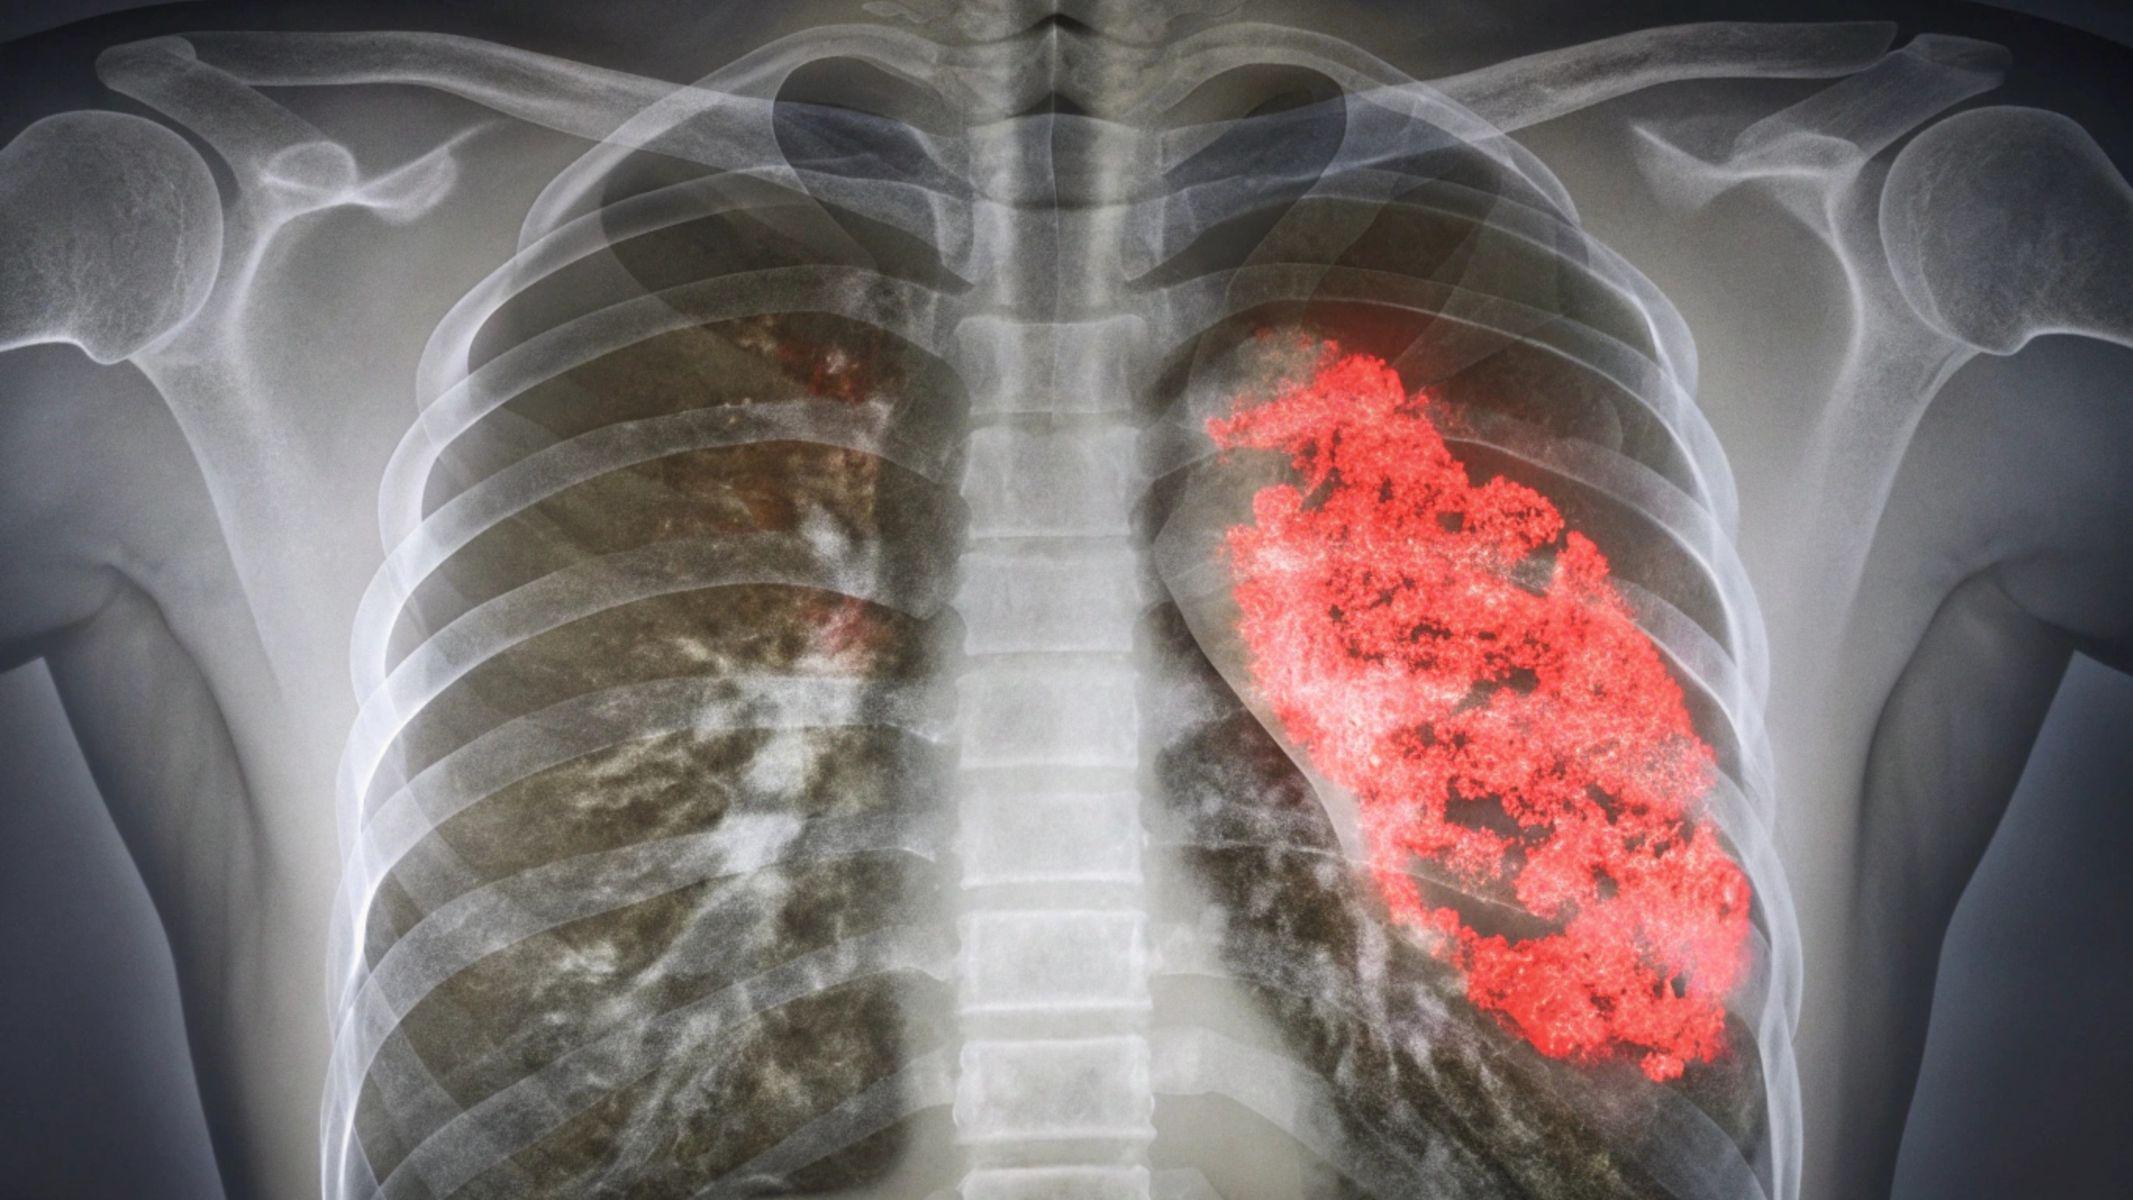

Về mặt y khoa, viêm phổi do RSV có thể dẫn đến suy hô hấp, rối loạn trao đổi khí và phải nhập viện để theo dõi, thở oxy hoặc hỗ trợ hô hấp. Dù tỷ lệ tử vong không cao, nhưng bệnh có thể gây biến chứng nặng nếu phát hiện muộn hoặc xử trí không đúng cách. Do đó, việc nhận biết sớm dấu hiệu cảnh báo và đưa trẻ đến cơ sở y tế khi cần thiết giúp hạn chế nguy cơ và bảo vệ sức khỏe hô hấp lâu dài cho trẻ.

Suy hô hấp là biến chứng nghiêm trọng và phổ biến nhất của viêm phổi do RSV. Virus gây viêm lan tỏa tiểu phế quản và phế nang, làm tăng tiết dịch nhầy, phù nề niêm mạc và hẹp lòng đường thở, từ đó cản trở quá trình trao đổi khí. Trẻ có thể xuất hiện thở nhanh, thở rút lõm lồng ngực, tím môi, đầu chi và giảm độ bão hòa oxy máu. Ở các trường hợp nặng, đặc biệt là trẻ dưới 6 tháng tuổi hoặc sinh non, suy hô hấp có thể tiến triển nhanh và cần hỗ trợ oxy hoặc thở máy.

ARDS là biến chứng nặng của viêm phổi do RSV, xảy ra khi tổn thương phổi lan rộng khiến phế nang chứa đầy dịch viêm và mất khả năng trao đổi oxy. Tình trạng này dẫn đến giảm oxy máu nghiêm trọng, không đáp ứng với thở oxy thông thường. Trẻ mắc ARDS thường cần thở máy và chăm sóc hồi sức tích cực. Nếu kéo dài, thiếu oxy có thể gây tổn thương các cơ quan quan trọng như não, tim, thận và làm tăng nguy cơ tử vong.